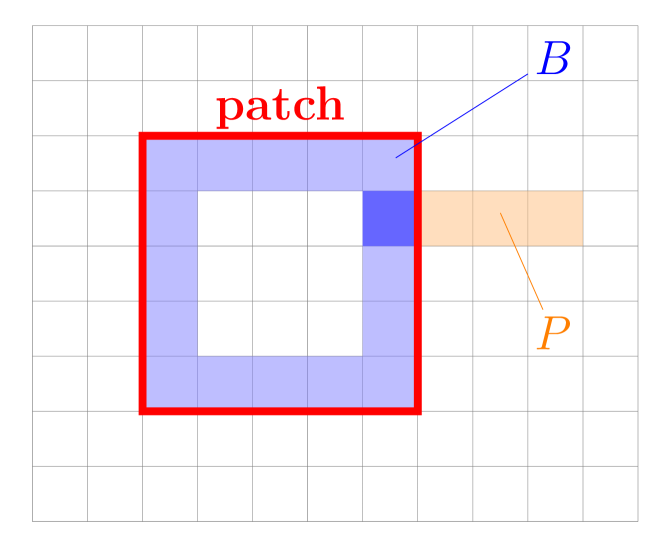

and consists of 3 parts: an image dissimilarity metric , a regularisation constraint for smoothness and to prevent folding as well as a cyclic constraint to encourage periodic deformations. and are weighting terms to control the influence of the regularisation terms. For the negative normalised cross correlation was adopted as it is known to perform well for mono modal image registration [37]. was chosen to be the l2-norm derivatives of the deformation field in combination with a boundary smoothness constraint to guarantee a homogeneous deformation field also at patch transitions:

with being the set of all 3D voxel positions, the number of phase images, the set of voxel positions at the border of an image patch and the set of neighbouring voxel positions along a given axis. For a better understanding we visualised the sets and in Fig. 2. controls the influence of the boundary smoothness constraint and calculates the Euclidean distance between positions and .